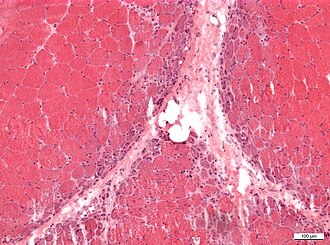

| H&E stain | routine, fibre size, shape, nuclei | H&E[15], H&E (WC) |

Microscopic

Features:

- Perifascicular inflammation with perifascicular atrophy - key feature.

- Loss of vessels around muscle fibres.

- Vessels should be where more than 3 or more fibres are opposed to one another.

Images

- Dermatomyositis - intermed mag.jpg

Dermatomyositis - intermed. mag. (WC)

- Dermatomyositis - high mag.jpg

Dermatomyositis - high mag. (WC)

- Dermatomyositis HE x40.jpg

Dermatomyositis - low mag. (WC)

- NP MGMT 0252.jpg

Dermatomyostits (WC/jensflorian)